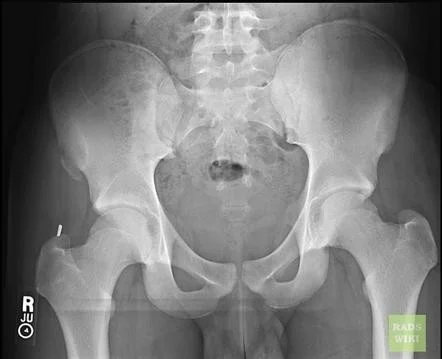

Primary Assessment

- A standard x-ray reveals up to 90% of fractures

Additional Imaging

- CT scan must be done for pelvis fracture to study condition of posterior ring